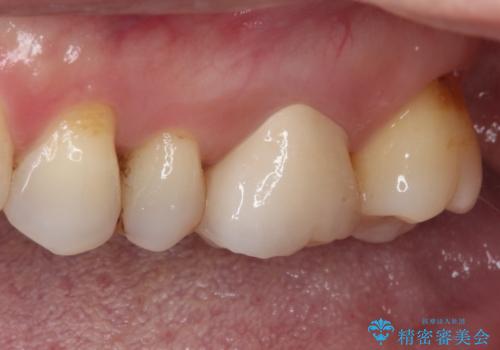

- 奥歯がしみる上に、変色が気になるとのことで来院された患者様です。

診査の結果、不適合なレジンインレーの隙間の接着剤が著しく変色しており、更には頬側の歯肉縁付近に知覚過敏症状が認められました。

健全歯質が多いため、インレーおよびむし歯を除去した上で知覚過敏を緩和させる処置を行うことが望ましいと判断されましたが、知覚過敏の症状が一向に改善されないため、全体をセラミッククラウンで補綴することとしました。